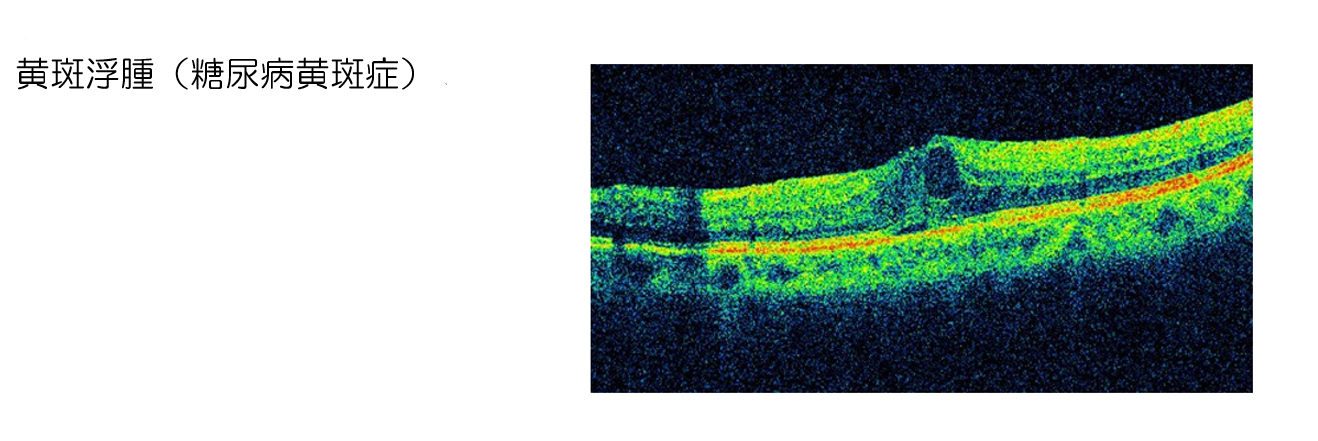

網膜浮腫により視力低下が進行した場合に選択される。